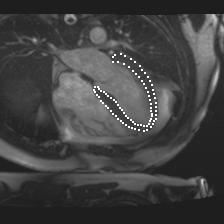

Accurate segmentation and motion estimation of myocardium have always been important in clinic field, which essentially contribute to the downstream diagnosis. However, existing methods cannot always guarantee the shape integrity for myocardium segmentation. In addition, motion estimation requires point correspondence on the myocardium region across different frames. In this paper, we propose a novel end-to-end deep statistic shape model to focus on myocardium segmentation with both shape integrity and boundary correspondence preserving. Specifically, myocardium shapes are represented by a fixed number of points, whose variations are extracted by Principal Component Analysis (PCA). Deep neural network is used to predict the transformation parameters (both affine and deformation), which are then used to warp the mean point cloud to the image domain. Furthermore, a differentiable rendering layer is introduced to incorporate mask supervision into the framework to learn more accurate point clouds. In this way, the proposed method is able to consistently produce anatomically reasonable segmentation mask without post processing. Additionally, the predicted point cloud guarantees boundary correspondence for sequential images, which contributes to the downstream tasks, such as the motion estimation of myocardium. We conduct several experiments to demonstrate the effectiveness of the proposed method on several benchmark datasets.